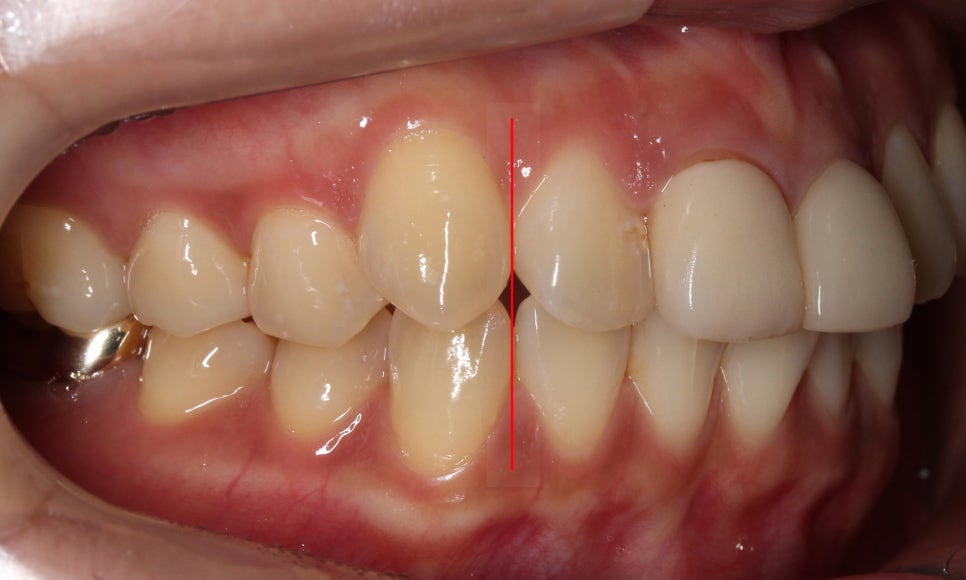

어금니 교합의 경우

치열의 삐뚤어짐으로 인해

상하악 어금니가 같은 위치로

맞닿아 물리는 모습인데요,

정상적인 치아교합의 경우

어금니가 톱니바퀴처럼

맞물리는 모습을 보이게 됩니다.

반대쪽 구치부 교합의 경우

비교적 양호한 교합 상태임을

확인할 수 있는데요,

전치부의 보철치료 후

치아착색으로 인해 자연치와

PFM크라운 사이의 경계가

명확하게 나누어져 보이는 모습입니다.